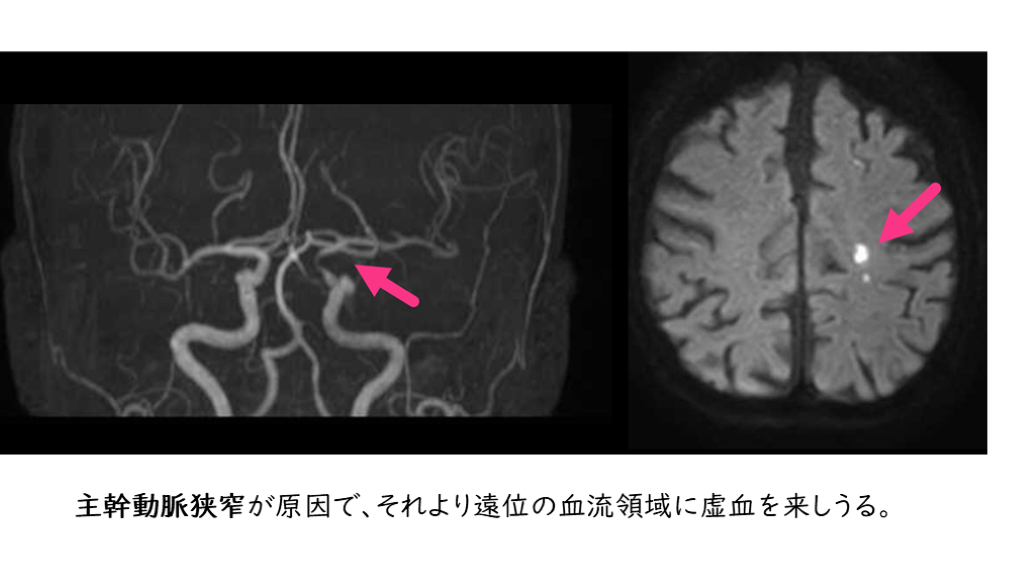

大血管の動脈硬化が問題 アテローム血栓性脳梗塞 アテローム性動脈硬化症により、脳に血液を供給する太い頭蓋外動脈および頭蓋内動脈内の狭窄をきたす。 これを、アテローム血栓性脳梗塞という。 神経症状は、しばしば変動、寛解、または途切れ途切れに進行する (階段状増悪という)。

血管狭窄病変があればそれより以遠の血流障害が起こり、脳梗塞を生じることはイメージしやすい。 血管狭窄が原因で血流障害をきたし、その血管支配領域の虚血に至る脳梗塞の発症機序を「血栓性機序」という。 アテローム血栓性脳梗塞は、血栓性機序の脳梗塞をきたす。 ラクナ梗塞も血栓性機序の脳梗塞。 アテローム血栓性脳梗塞は一言でいうと、 動脈硬化により、 「太い血管が細くなって起こる脳梗塞」です。

アテローム血栓性脳梗塞の発症機序

主幹動脈狭窄が原因で、それより遠位の血流領域に虚血を来しうる。

定義:「虚血病巣を還流する血管に 50%以上の狭窄がある」